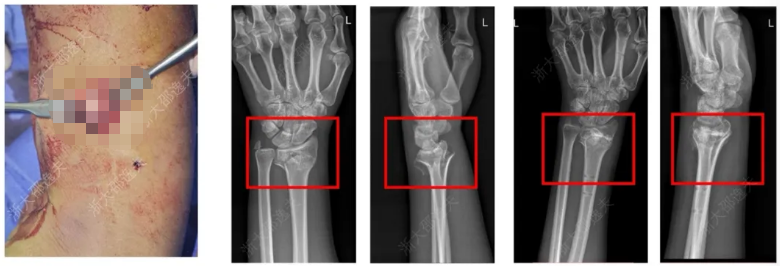

一位年轻工人因外伤导致腕部桡骨远端粉碎性骨折,传统治疗方案需大切口植入钢板螺钉,不仅创伤大、存在肌腱粘连或神经损伤风险,且需术后一年行二次手术取出。

桡骨远端骨折金属内固定治疗病例

应用“骨02”黏合技术,仅通过微创切口注入“胶水”材料,短短3分钟内即完成了粉碎骨块的精准黏合与固定。术后3个月随访显示,患者骨折愈合良好,无并发症,腕关节功能完全恢复。

桡骨远端骨折通过“骨02”治疗病例